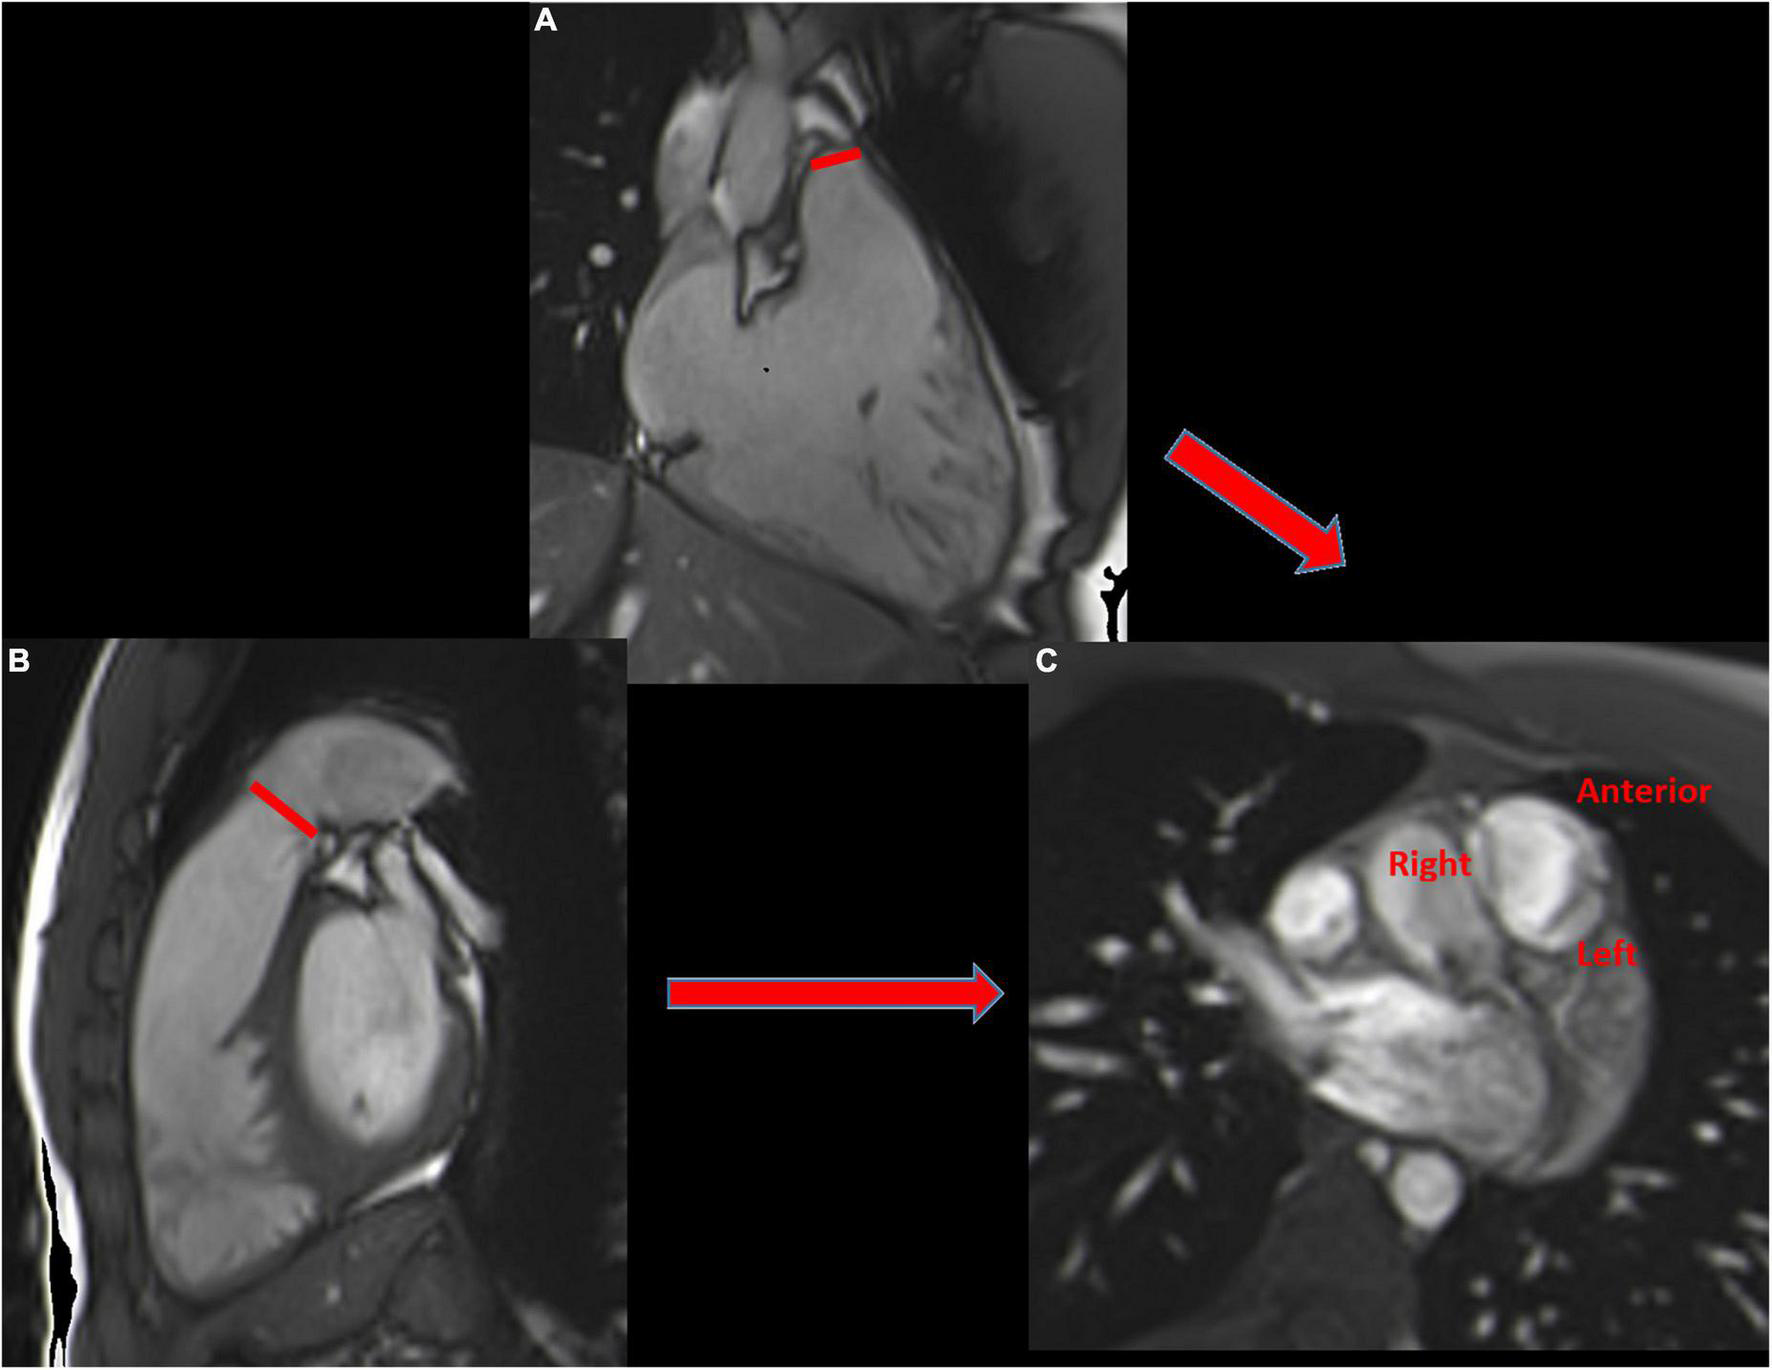

FIGURE 6

Cardiovascular magnetic resonance planes used for evaluation of the right ventricle. Short axis view (A), 3-chamber view (B) and RVOT (C). Example of tricuspid annular measurement in the 4-chamber view (red line) (D).

Tricuspid anatomy can be assessed by short- and long-axis views, as already described, allowing simultaneous visualization of the three leaflets (septal, anterior, and posterior) in the short-axis view. Leaflets can be described as prolapsed, restricted, thickened, or with tenting (77). Tenting height and area may be measured and considered abnormal if they are > 7 mm (3 mm/m2) and 1.1 cm2 (> 0.5 cm2/m2), respectively (14). However, tricuspid leaflets are thin, as well as the chordae and papillary muscles, and can be difficult to visualize. Therefore, echocardiography remains the cornerstone for TR anatomy assessment.

The tricuspid annular diameter, a relevant parameter included in the guidelines for tricuspid intervention, can be measured in the 4-chamber view in early diastole, with the upper limits of the normal value recently reported to be 43 mm (22 mm/m2) (78) (Figure 6). It is important to note that for patients with pacemakers or defibrillator leads, generated metallic artifacts decrease the accuracy of CMR for the assessment of RV volume structure and tricuspid anatomy, as well as for patients with arrhythmias.